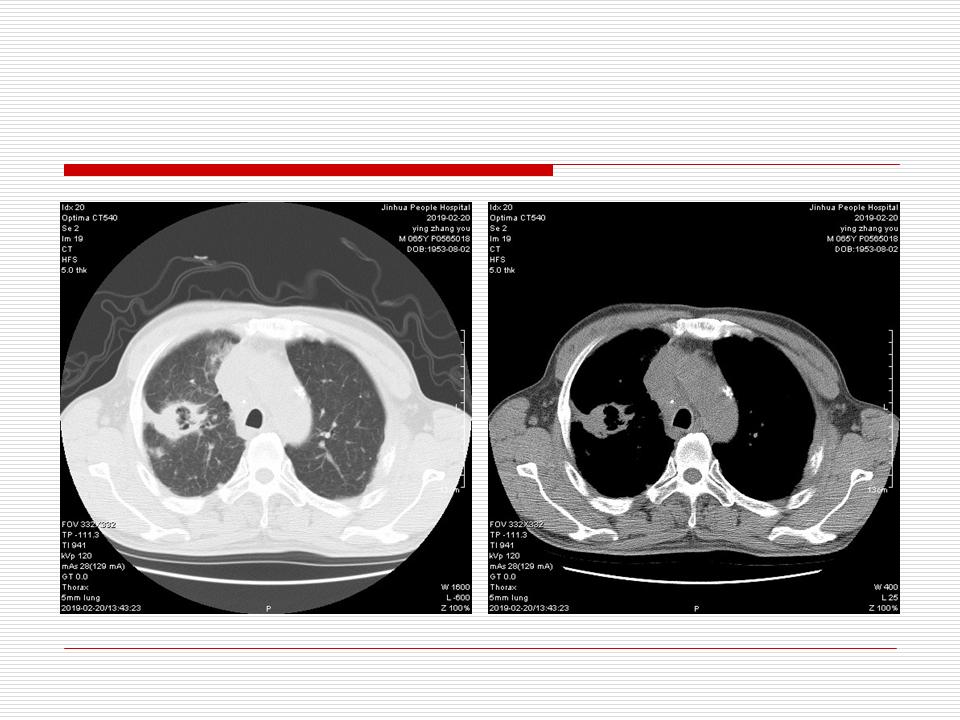

肺部阴影永恒且最重需要鉴别的是:到底是炎症还是肿瘤?但临床的病例中的影像表现难以界定或有些肿瘤特征,同时又有些炎症特点是非常常见的情况。作为临床医生我们怎么去总结分析,并找到之所以是炎症或之所以是肿瘤的细微差别或特点非常重要,也非常有用。2019.12.7浙江省2019年胸心外科学学术年会在宁波召开时,我的临床病例分析与经验总结<那些像肺癌的炎症与像炎症的肺癌>获得在大会交流的机会,以下为该PPT的内容,与你分享,希望对同道有益,有借鉴与启迪。若有探讨与进一不完善的建议,欢迎文末留言讨论: